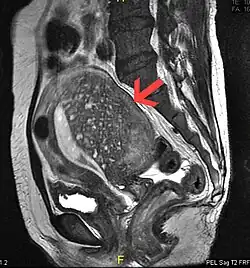

Magnetic resonance imaging

Magnetic resonance imaging (MRI) provides slightly better diagnostic capability compared to TVUS, due to the increased ability of MRI to differentiate objectively between different types of soft tissue.[24] This is possible with MRI's higher spatial and contrast resolution. Overall, it is estimated that MRI has a sensitivity of 74% and specificity of 91% for the detection of adenomyosis.[11] Diagnosis through MRI focuses predominately upon investigating the junctional zone. The uterus will have a thickened junctional zone with darker/diminished signal on both T1 and T2 weighted sequences.[24]

Three objective measures of the junctional zone can be used to diagnose adenomyosis.[24]

- A thickness of the junctional zone greater than 8–12 mm. Less than 8 mm is normal.

- A junctional zone width being greater than 40% of the width of the myometrium.

- Variability in the width of the junctional zone being greater than 5 mm.

Interspersed within the thickened, darker signal of the junctional zone, one will often see foci of hyperintensity (bright spots) on the T2 weighted scans representing small cystically dilatated glands or more acute sites of microhemorrhage.[24]

MRI is limited by other factors, but not by calcified uterine fibroids (as is ultrasound). In particular, MRI is better able to differentiate adenomyosis from multiple small uterine fibroids.